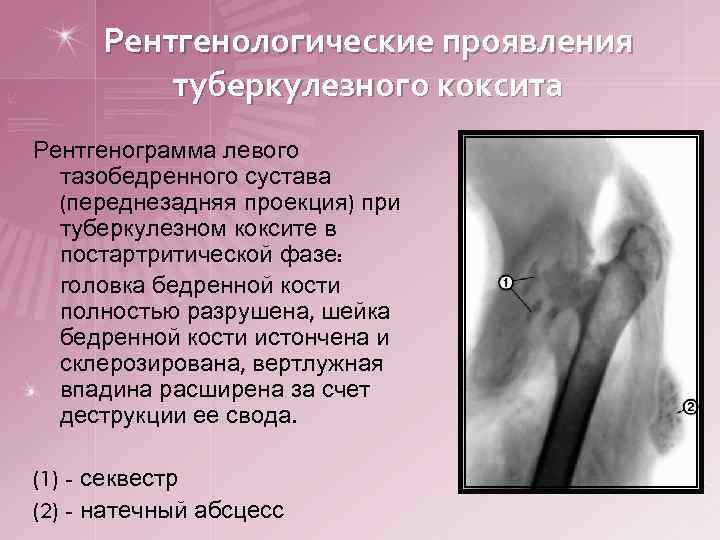

Рентгенологические проявления туберкулезного коксита Рентгенограмма левого тазобедренного сустава (переднезадняя проекция) при туберкулезном коксите в постартритической фазе: головка бедренной кости полностью разрушена, шейка бедренной кости истончена и склерозирована, вертлужная впадина расширена за счет деструкции ее свода. (1) - секвестр (2) - натечный абсцесс